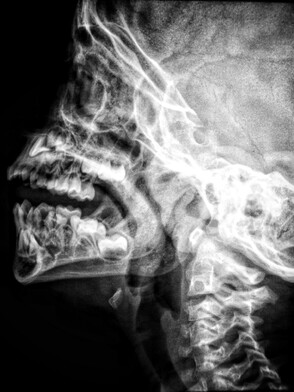

Sunshine Coast Chiropractor TMJ treatment

TMJ (Temporomandibular Joint) disorder is a common condition that affects the jaw joint and its surrounding muscles. Symptoms of TMJ disorder include pain and discomfort in the jaw, neck, and face, difficulty chewing, and clicking or popping sounds when opening and closing the mouth.

At Little Mountain Chiropractic, our treatment involves a holistic approach to healthcare that seeks to address the underlying cause of a condition, rather than simply treating its symptoms. In the case of TMJ disorder, chiropractors will often use a combination of manual therapy techniques, such as joint mobilisation, stretching and manipulation, to improve the function of the jaw joint (TMJ) and surrounding muscles. This can help to reduce pain, increase range of motion, and improve overall jaw function.